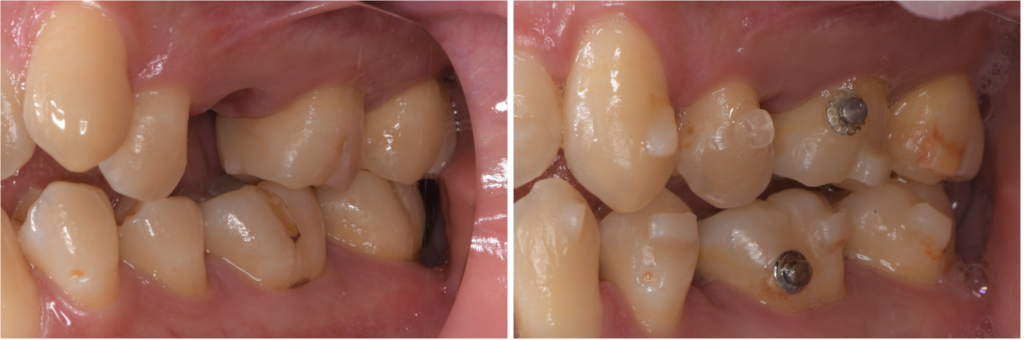

銀歯を白くする治療で失敗しないために──“接着”と“噛み合わせ”が運命を決める理由

「銀歯を白くしたい」「口を開けたときに金属が見えるのが気になる」このようなお悩みからセラミック治療を検討される方は非常に多くいらっしゃいます。とくに40代以降の女性の患者さまは、見た目はもちろん、“健康面として歯を…